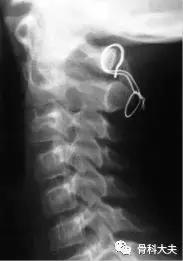

Gallie法融合

目前,还可采用更加坚强的螺钉作为内固定,主要有两种手术方式:Magerl穿关节螺钉或寰枢椎的钉杆系统内固定。需依据病人的局部解剖情况、医生的习惯来选择具体的手术方式。

C1/2钉杆系统和Magerl螺钉